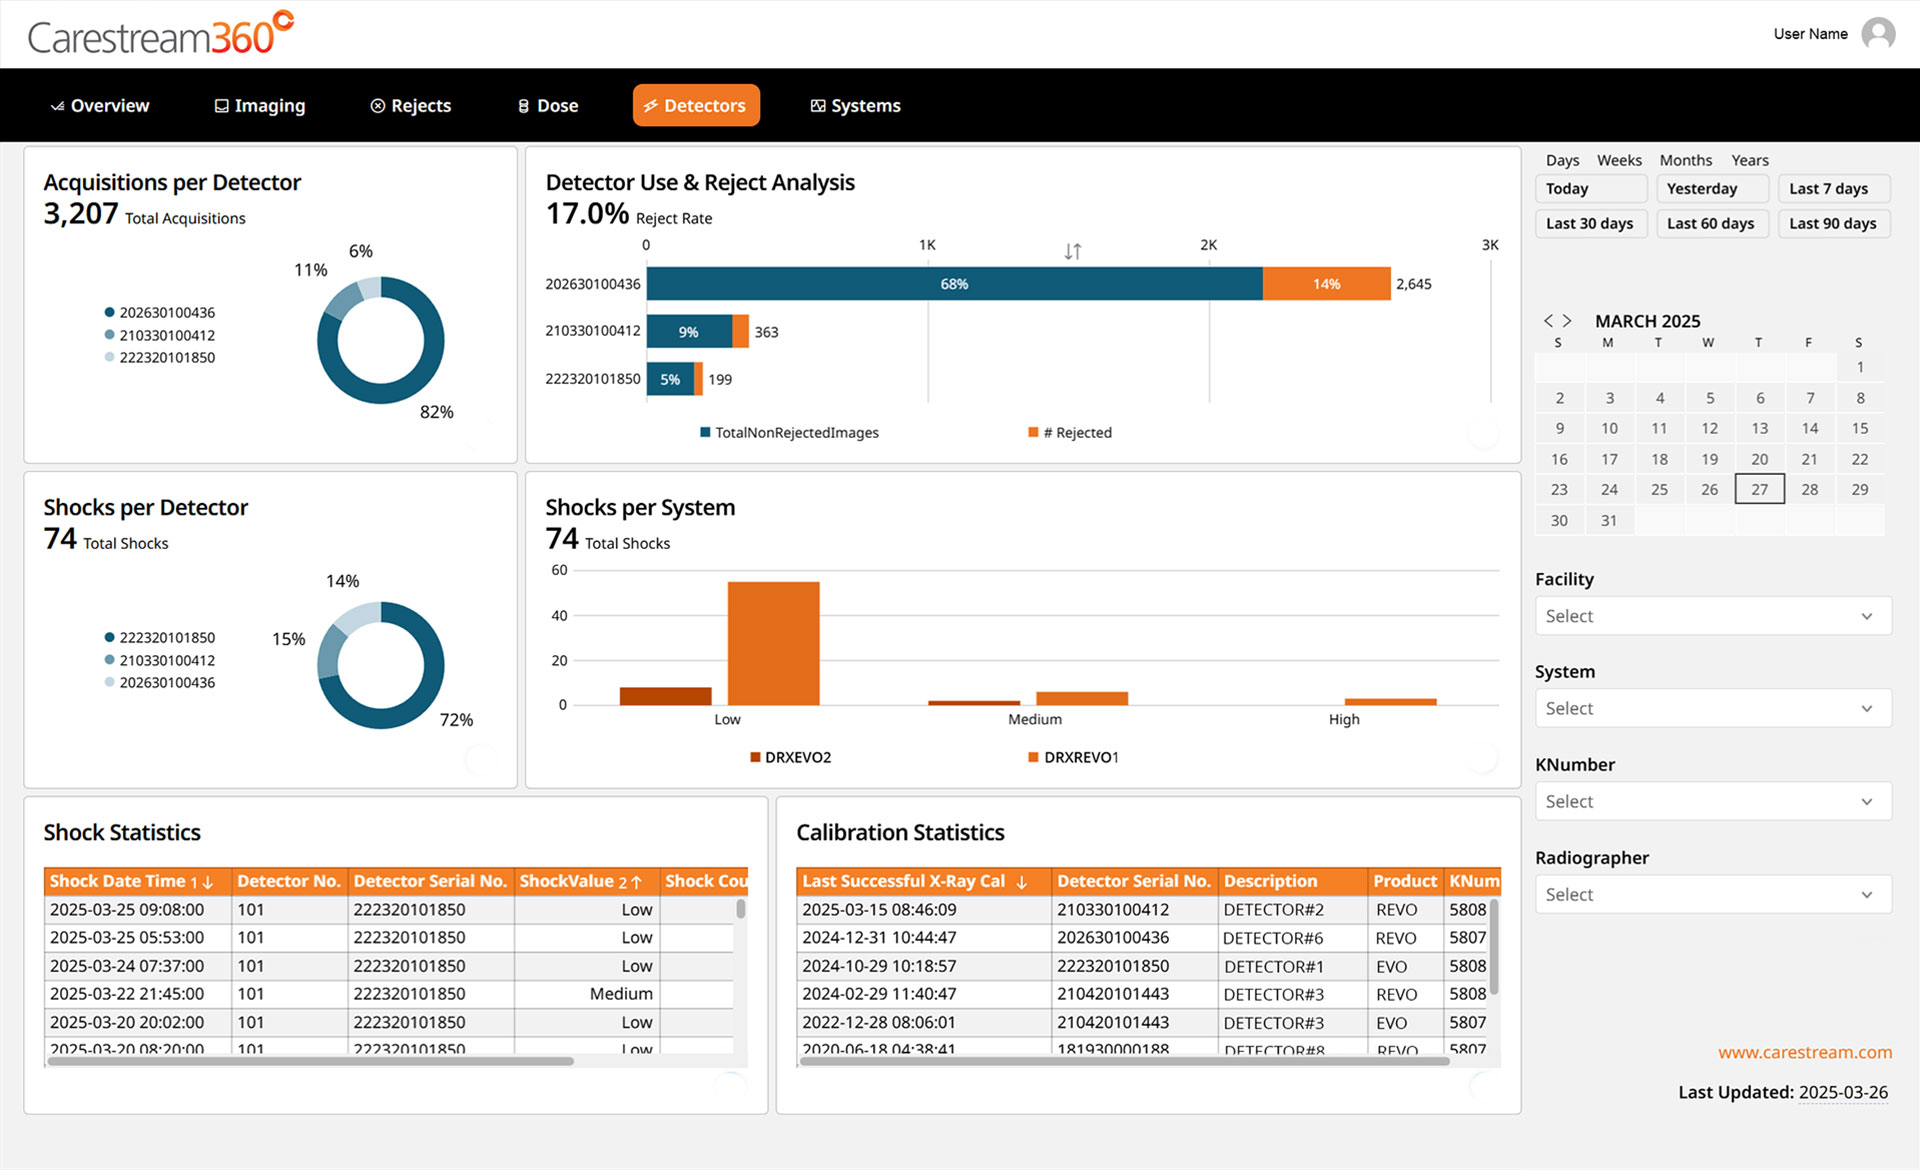

Carestream 360º is an advanced analytics dashboard designed to help radiology departments track key performance metrics, analyze imaging trends, and optimize operational efficiency. It automatically collects critical data from all connected Carestream DR systems and consolidates it into a single, intuitive dashboard, providing a comprehensive view to drive smarter decision-making.

Carestream 360º is designed with interactive tools that allow you to filter, explore, and export data effortlessly, empowering you to gain insights faster, interact intuitively, and make informed, data-driven decisions.

- Filter with Ease – Quickly refine data using intuitive, pre-set filters that allow you to focus on the metrics that matter most.

- Drill-Down Analysis – Dive deeper into trends and performance metrics to support more informed decision-making.

Key Insights to Optimize Performance

Carestream 360º transforms complex performance metrics into clear, actionable insights through a series of intuitive dashboard pages. Designed for efficiency, it helps you: